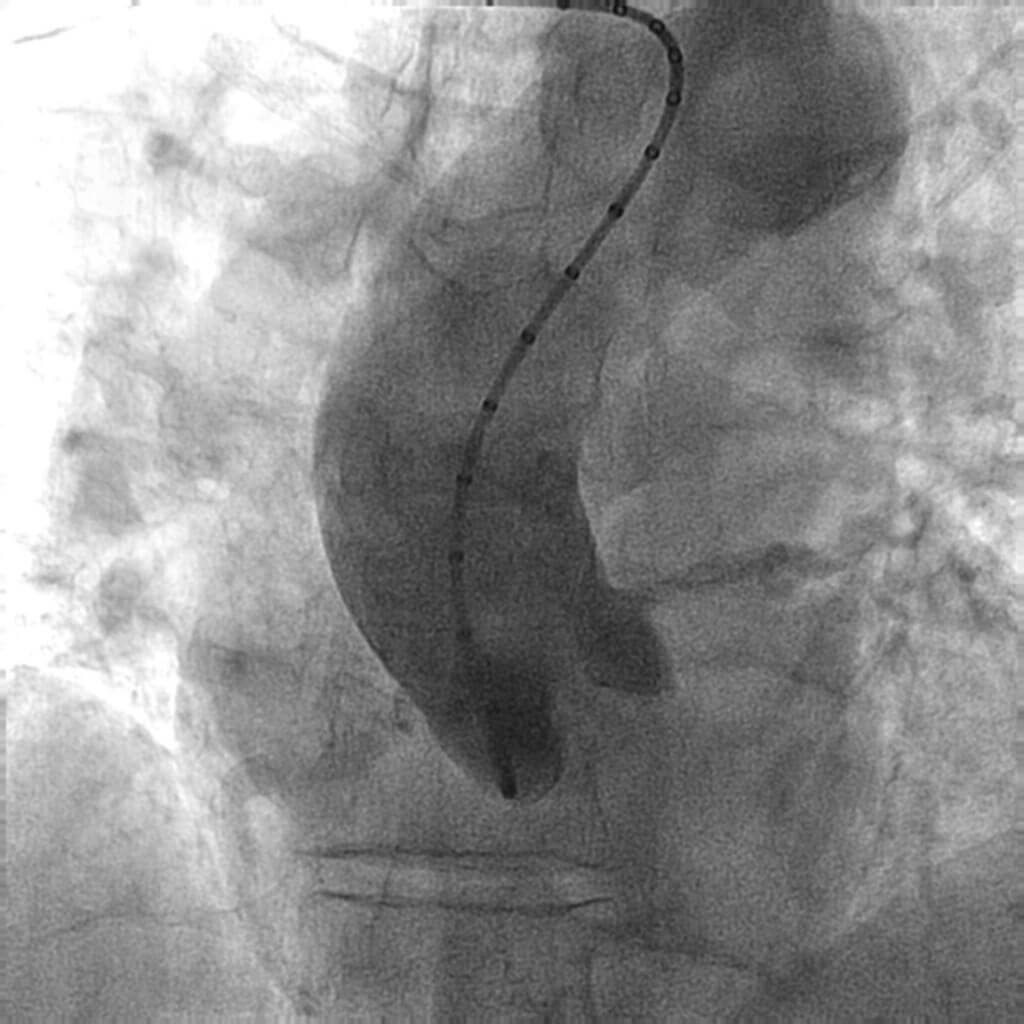

Se completó el estudio mediante coronariografía, en la que se observó enfermedad arterial coronaria del tronco común y de 2 vasos: tronco común largo y calcificado con lesión distal al límite de la significación que afectaba la bifurcación con la descendente anterior, 2 ramas intermedias y la circunfleja; la descendente anterior con lesión grave y calcificada ostial, primera y segunda ramas intermedias con lesiones significativas y calcificadas ostiales, y la circunfleja con lesión moderada ostial (figura 1, figura 2 y vídeo 1 del material adicional) con vaso distal de fino calibre y escaso recorrido. El aortograma mostró una válvula aórtica trivalva y calcificada, con apertura de los velos limitada e insuficiencia aórtica ligera; raíz aórtica y aorta ascendente no dilatadas y sin ateromatosis significativa (figura 3 y vídeo 2 del material adicional). La arteriografía de miembros inferiores mostró un eje ilíaco-femoral no calcificado ni tortuoso, con un diámetro mínimo de 7,3 mm en la arteria femoral común derecha y un diámetro mínimo de 7,7 mm en la arteria femoral común izquierda. Se calculó un riesgo a corto plazo de la Society of Thoracic Surgeons del 10,79%.

Figura 3. Aortograma que muestra la válvula aórtica trivalva con moderada calcificación de los velos, raíz aórtica y aorta ascendente no dilatadas, y sin ateromatosis significativa.